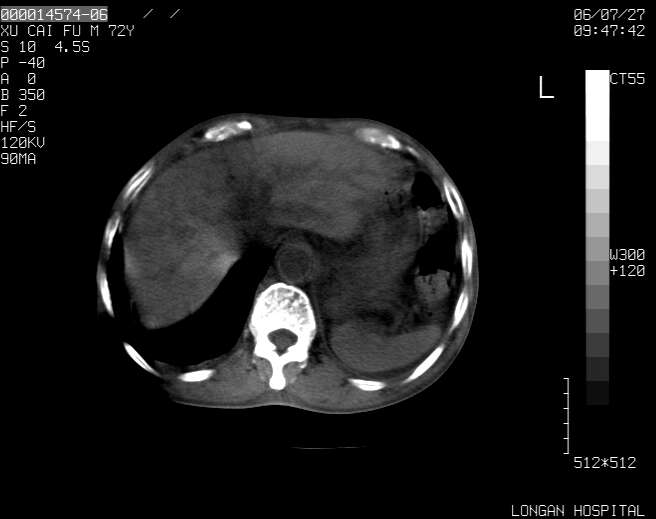

以下是引用winter在2006-7-30 20:14:00的发言:[br]1、考虑胆囊癌伴胆道侵犯并高位胆道梗阻、肝内多发转移、腹膜后淋巴结转移。[br]2、右肾轻度积水。[br]3、老人家72岁了胰腺头体尾部均较饱满,不过未见密度异常及其他异常征象。[br]4、腹水。

以下是引用jiajie在2006-7-31 7:10:00的发言:[br]考虑肝转移瘤,腹膜后淋巴结增大。[br]胃癌不能除外,建议胃镜检查。